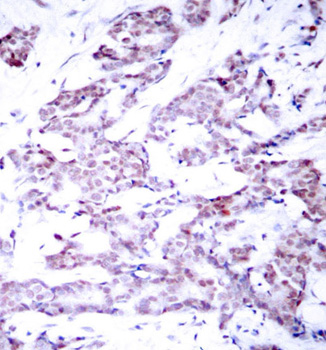

• AP0455: image 1

Immunohistochemical analysis of paraffin-embedded human breast carcinoma tissue, using Phospho-STAT6-T645 antibody.